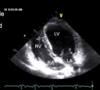

this is long-axis view of the right sige

what view? and ID them

left 4 chamber view

this view is short-axis

for short axis view of R side, marker dot position should be

this is short axis view of the right side